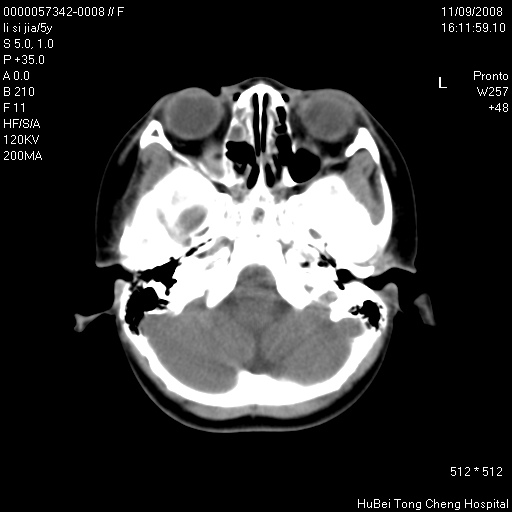

患儿 女,5岁。鼻塞、流涕2年余。

临床诊断:慢性副鼻窦炎?

副鼻窦ct轴位平扫(层厚、层距均为5mm),图像如下:

双侧上颌窦\\筛窦及蝶窦内均可见多量软组织密度影,结合病史支持考虑慢性全鼻窦炎

双侧上颌窦、筛窦及蝶窦内均可见粘膜增厚,结合病史支持考虑慢性全付鼻窦炎,腺样体肥大。